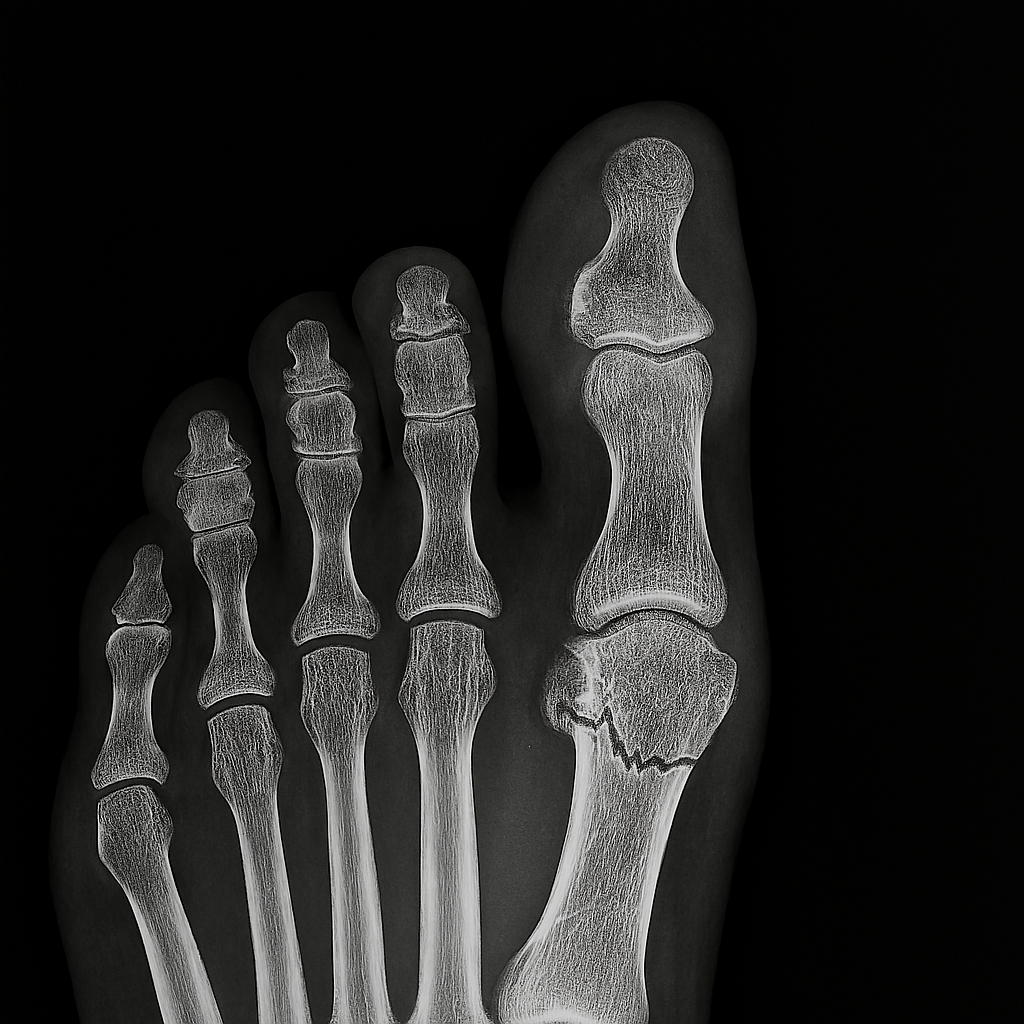

Athletic movement involves high-load, high-velocity actions that place extreme stress on joints, muscles, and connective tissues. Sprinting, jumping, pivoting, and tackling all generate forces that exceed normal physiological thresholds. Ligaments such as the anterior cruciate are particularly vulnerable in sports requiring rapid deceleration and directional change. Muscle strains often result from eccentric contractions – where the muscle lengthens while under tension, creating microscopic damage. Tendons can degenerate over time due to repetitive loading – leading to chronic conditions like tendinopathy. Bone stress injuries emerge when cumulative force exceeds the bone’s ability to remodel – often seen in long-distance runners. The kinetic chain – the interconnected system of joints and muscles – can fail when one segment compensates for another, increasing injury risk. Poor biomechanics, even in elite athletes, can amplify vulnerability. Injury is not just a failure of tissue – it’s a signal of systemic overload and imbalance.

The Role of Elite Medical Support

Professional athletes have access to multidisciplinary medical teams that optimize every phase of recovery. Sports physicians, physiotherapists, orthopedic surgeons, and nutritionists collaborate to create individualized treatment plans. Diagnostic imaging such as MRI and ultrasound allows precise identification of tissue damage – guiding targeted interventions. Surgical techniques are often minimally invasive – reducing recovery time and preserving function. Rehabilitation protocols are progressive and evidence-based – incorporating strength, mobility, proprioception, and sport-specific drills. Manual therapy, dry needling, and neuromuscular re-education accelerate tissue remodeling. Nutrition is tailored to support healing – with emphasis on protein synthesis, anti-inflammatory compounds, and micronutrient balance. Recovery is monitored through biomarkers, performance metrics, and subjective feedback. This level of care is rarely available to the general public – creating a disparity in recovery outcomes.